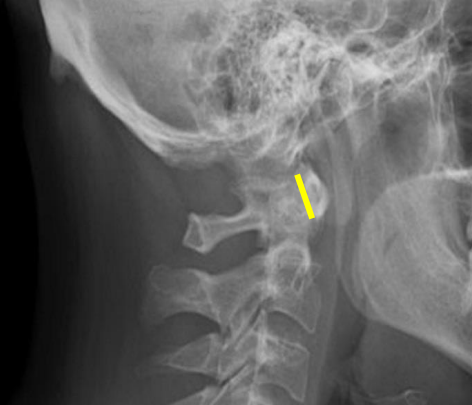

Odontoid process

C2 spinous process

C2 pedicle shadow